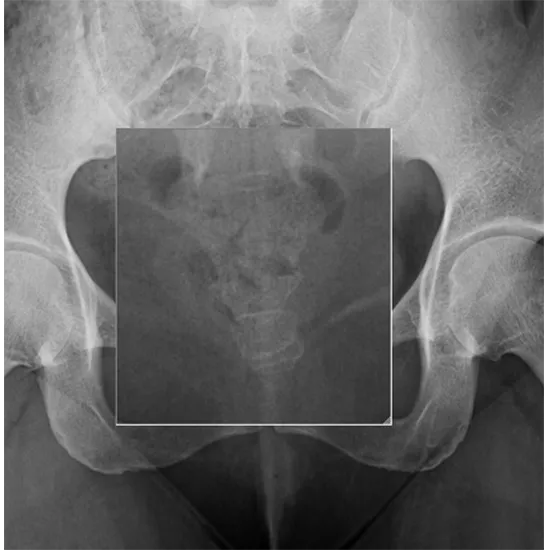

The AP view of the coccyx is used to show how it fits in with the sacrum and coccyx. The side (lateral) view of the coccyx is used to show the attached point of the spine in a side position. The lateral view of the coccyx is used to look at the most backward part of the spine. It works together with the AP projection.

The X-ray Coccyx (AP / LAT View) Test is used to show how the sacrum and coccyx are put together and find the cause of short-term and long-term pain in those areas.